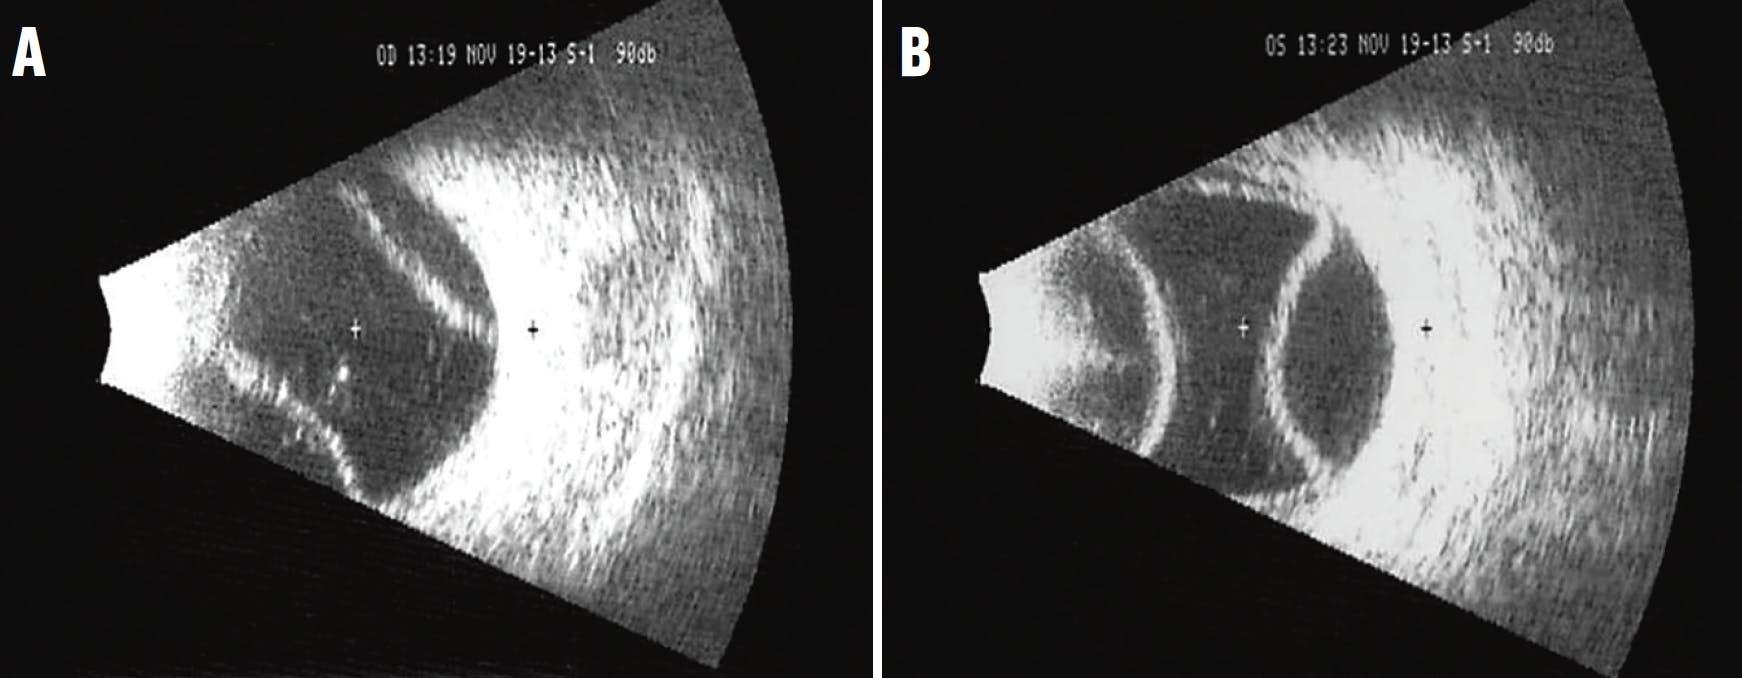

At presentation, his BCVA was 20/70 OD and 20/100 OS, and his IOP was 17 mm Hg OD and 20 mm Hg OS. The anterior chamber in each eye was deep and quiet, notable only for the ACIOLs. There was no vitritis or vitreous haze in either eye. Fundus examination of each eye showed moderate-sized serous choroidal detachments in the temporal and nasal periphery and multiple choroidal hemorrhages in the nasal periphery (Figure 1). B-scan ultrasonography confirmed the serous nature of the choroidal detachments and revealed a normal axial length in each eye (Figure 2).

<p>Figure 2. B-scan ultrasound images confirmed the serous nature of the choroidal detachments in the right (A) and left (B) eye.</p>

Figure 2. B-scan ultrasound images confirmed the serous nature of the choroidal detachments in the right (A) and left (B) eye.